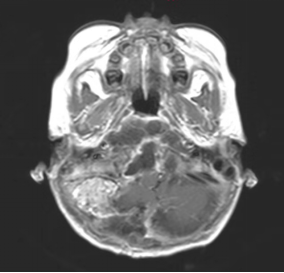

通常情况下,小孩子很少打鼾(俗称打呼噜),如果您的宝宝睡觉打鼾,并且声音很大,那要引起注意了,最好带孩子做个检查,因为睡觉打鼾也有可能是脑肿瘤引起的。